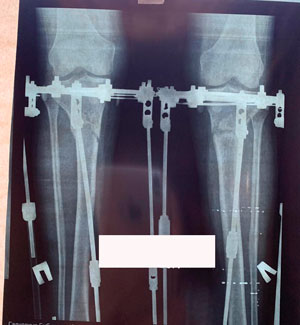

Перед крутками

Рентген в 60 дней

рентген в 90 дней.